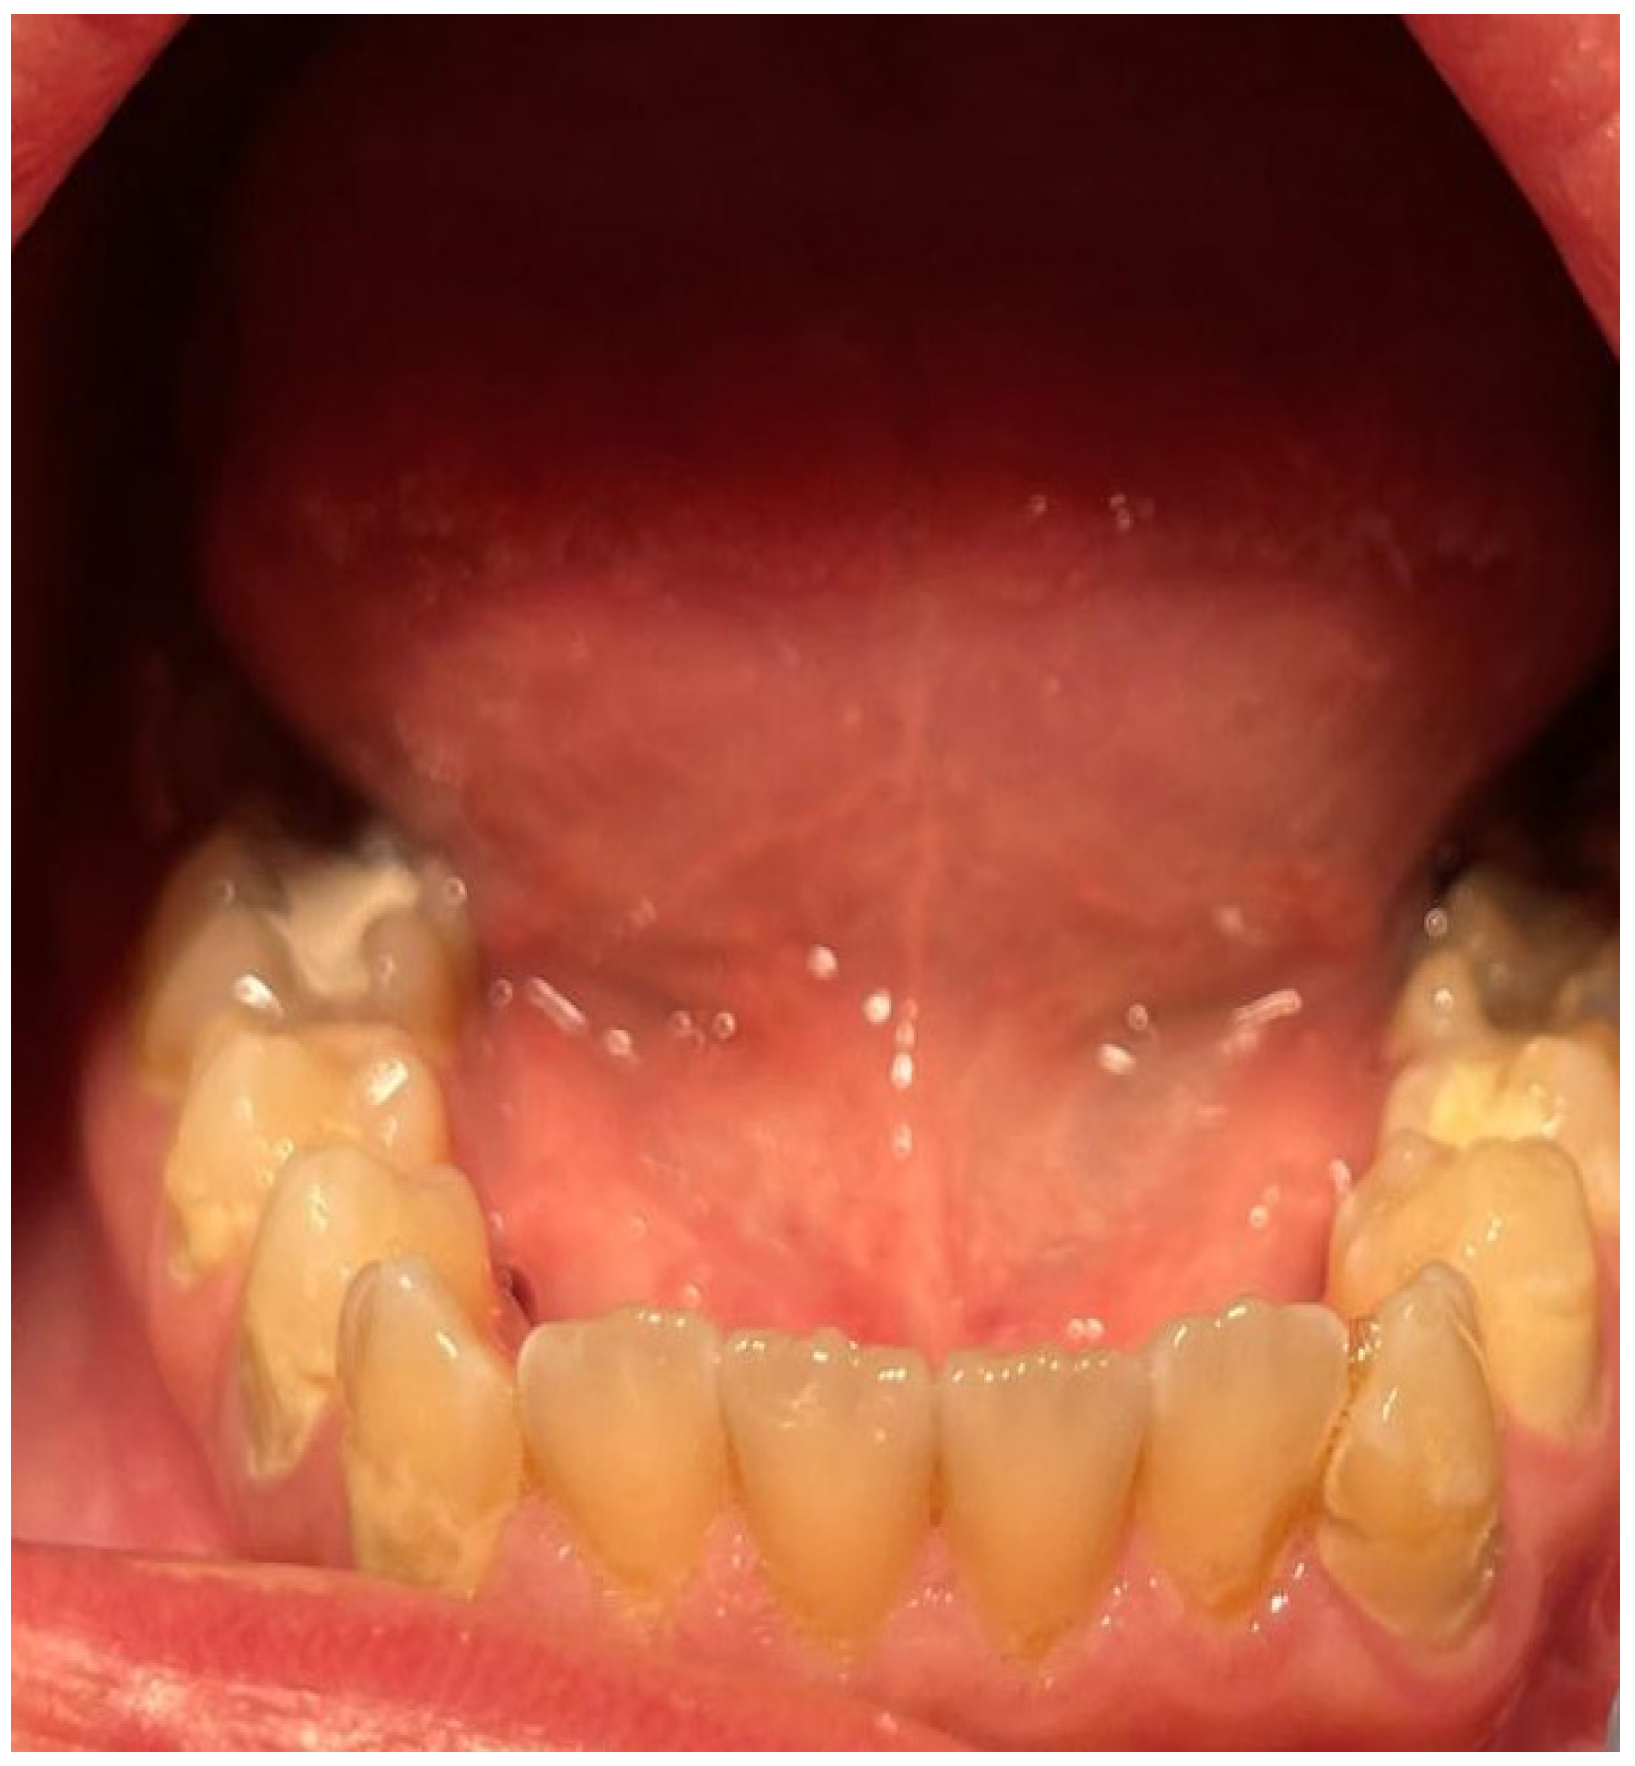

2. Case Report